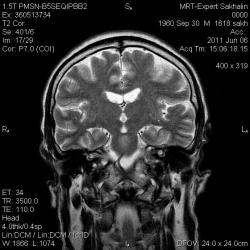

Обещанный случай.Выбрала по одному показательному скану.Что скажете?

04.06.2011 - 16:28

Женщина, 51 год. Около года беспокоит периодически головная боль, головокружения, "приливы крови" к голове. Очаговой симптоматики нет. В апреле сделала МРТ, нашли образование. Обследуется у...